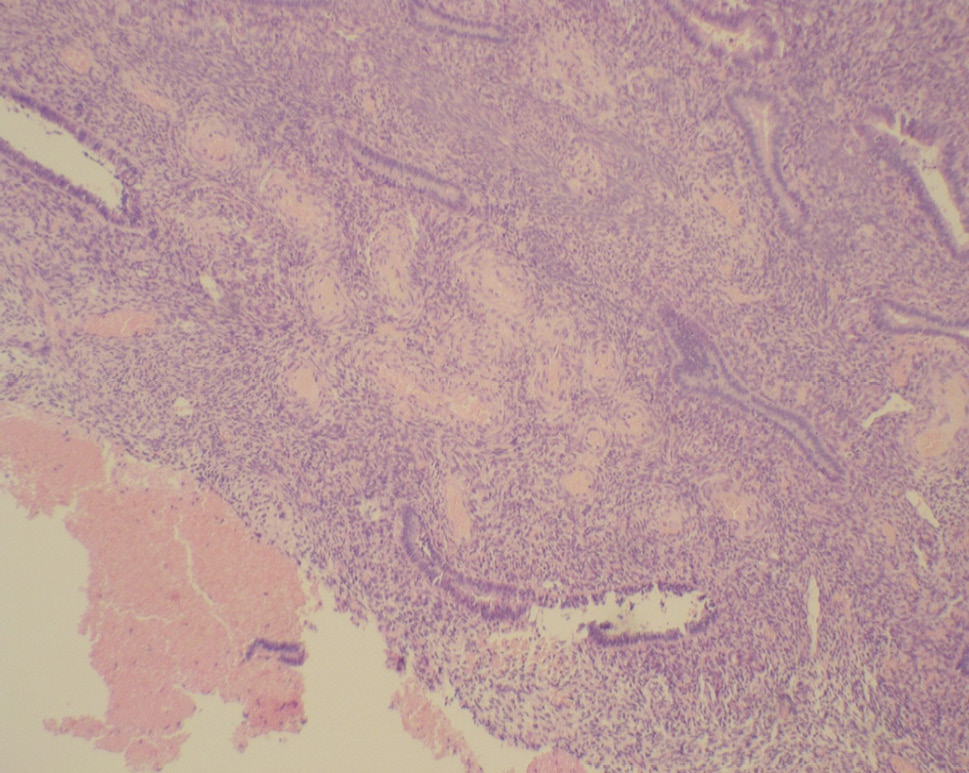

- During a hysteroscopic examination, endometrial polyps were visualized in 43.3% of cases. The main complaint was abnormal uterine hemorrhage. Oval pale pink formations with a smooth surface and slight vascularization on the pedicle were determined hysteroscopically. Large endometrial polyps (1.5–2.0 cm) were detected in 20.7% of cases, medium polyps (1.0 cm) were found in 78.5% of cases. In patients of this age group, glandular-fibrous and fibrous polyps prevailed (62.8%) in the shape of formations on the pedicle with cystic-dilated glands (Fig. 4).

Fig. 4. Glandular fibrous endometrial polyp of the senile type with cystic expansion of the glands and severe circulatory disorder (hematoxylin and eosin staining at ×40 magnification)

Рис. 4. Железисто-фиброзный полип эндометрия «сенильного типа» с кистозно расширенными железами и выраженным расстройством кровообращения (окраска гематоксилином и эозином, увеличение ×40)